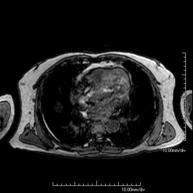

Prueba diagnóstica no invasiva que consiste en la obtención de imágenes de alta definición anatómica del mediastino mediante el empleo de un campo electromagnético y ondas de radio (con un emisor y un receptor). No utiliza radiación ionizante. El mediastino es la parte central de la caja torácica que incluye el timo, los grandes vasos (aorta torácica, vena cava inferior y superior, etc.), el corazón, la tráquea y los bronquios principales, ganglios linfáticos mediastínicos e hiliares, el esófago, etc. Está especialmente indicada en lesiones mediastínicas para diferenciar si son quísticas o sólidas, en el diagnóstico diferencial de las lesiones del mediastino anterior, etc. En ocasiones se deberá emplear contraste paramagnético (Gadolinio) para completar el estudio. - RM Tórax

Prueba diagnóstica no invasiva que consiste en la obtención de imágenes de alta definición anatómica del tórax mediante el empleo de un campo electromagnético y ondas de radio (con un emisor y un receptor). No utiliza radiación ionizante. Está indicada en aquellas lesiones pulmonares en las que debe descartarse si existe infiltración del mediastino o de la pared torácica, para diferenciar si una lesión torácica es sólida o quística, etc. En ocasiones se deberá emplear contraste paramagnético (Gadolinio) para completar el estudio. - RM Pared Torácica